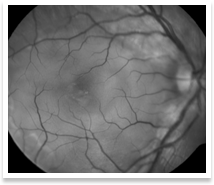

This refers to inflammation within the eye ball. It can involve the anterior portion of the eye(iritis, iridocyclitis or anterior uveitis), the middle portion of the eye(vitritis, intermediate uveitis or pars planitis) or the back portion of the eye(retinitis, retino-choroiditis or choroiditis or posterior uveitis) or the optic nerve, which carries visual information from the eye to the brain(optic neuritis). In many cases, the exact cause cannot be determined. Treatment consists of systemic steroids. Recent advances in ocular disease management enable us to give steroid injections around the eye or even within the eye itself. This has the advantage of avoiding bodily complications of systemic(tablets or intravenous injections) steroids

Uveitis can lead to other complications such as cataract, glaucoma and retinopathy or retinal detachment